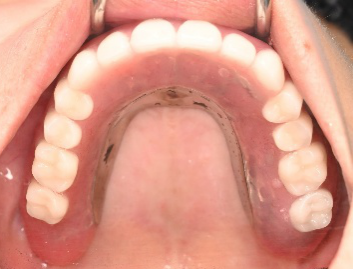

Before

赤丸2本は、歯根破折を起こしていたため抜歯しました。

After

【義歯を装着したところ】

【義歯を外したところ】